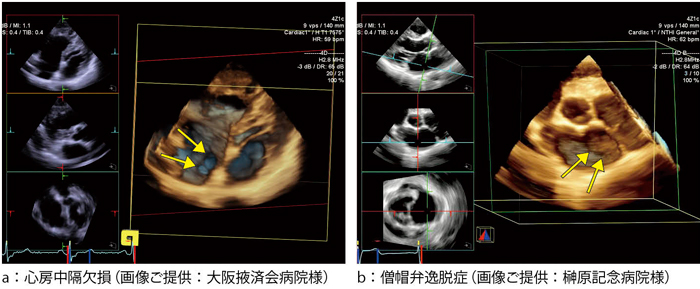

PVX Ver.2|精密超音波厚さ計|ダコタ・ジャパン, ACUSON SC2000」によるリアルタイムFull Volume Imagingの活用法 - 技術解説 - シーメンス・ジャパン株式会社 - inNavi Suite,

ACUSON SC2000」によるリアルタイムFull Volume Imagingの活用法 - 技術解説 - シーメンス・ジャパン株式会社 - inNavi Suite, ZX-1 / ZX-2|超音波厚さ計|ダコタ・ジャパン